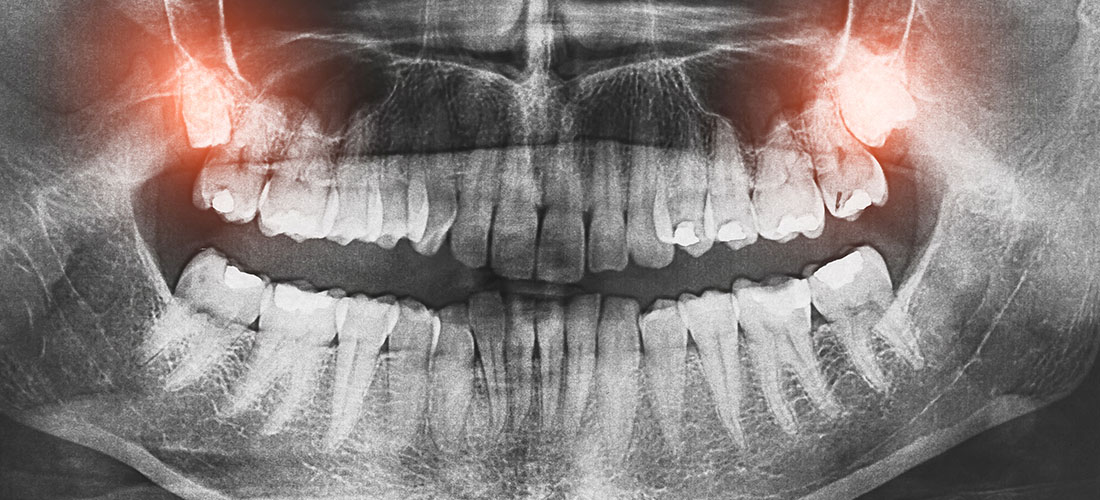

Wisdom Teeth Extractions

Removal of impacted or problematic wisdom teeth to prevent pain and infection.

✔ Treat impacted wisdom teeth before complications arise